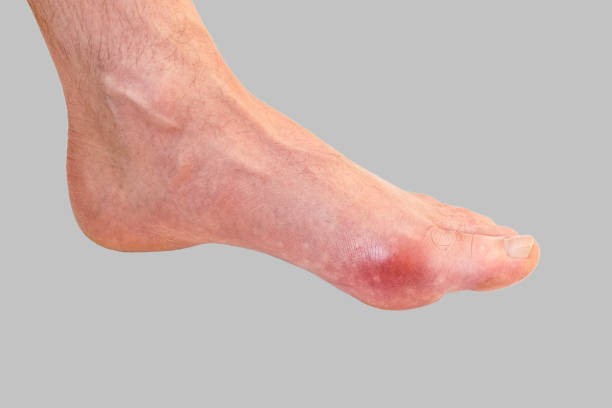

통풍 증상은 그 시기에 따라 고요산혈증, 급성 통풍성 관절염, 간헐기 통풍 등 3가지 단계로 나눌 수 있으며 전형적 증상은 갑자기 엄지발가락 부위가 조금 뻐끈하다는 느낌으로 시작하며 이 부위가 급격히 붓고 통증이 심해지면 관절 주변 피부가 일어나면 열감이 느껴지고 종국에는 신발을 신을 수 없을 정도로 극심한 통증을 겪게 됩니다.

급성 통풍성 관절염은 한 개 관절에서만 나타나는데 아무래도 그 부위는 엄지발가락에서 나타나며 발 관절인 발등, 발목, 무릎 그리고 나아가서는 손목에서도 나타납니다. 통풍이 발현하면 10일 정도 지속되는데 완화가 되더라도 재발 및 악화되는 경우가 있어 치료를 받아야 합니다. 간헐기 통풍은 일반적으로 6개월에서 2년 사이 두 번째 발작이 나타나는데 통풍 발작은 치료를 받지 않으면 그 가능성이 높아져 시간이 지나면 여러 관절들로 퍼질 수 있어 반드시 치료를 받아야 하며 평상시 요산 수치를 조절해야 합니다.